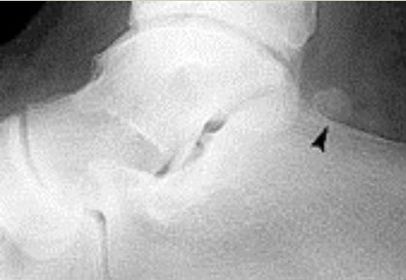

| What is this? | Calcaneonavicular coalition (AKA calcaneonavicular bar or anteater's nose) |